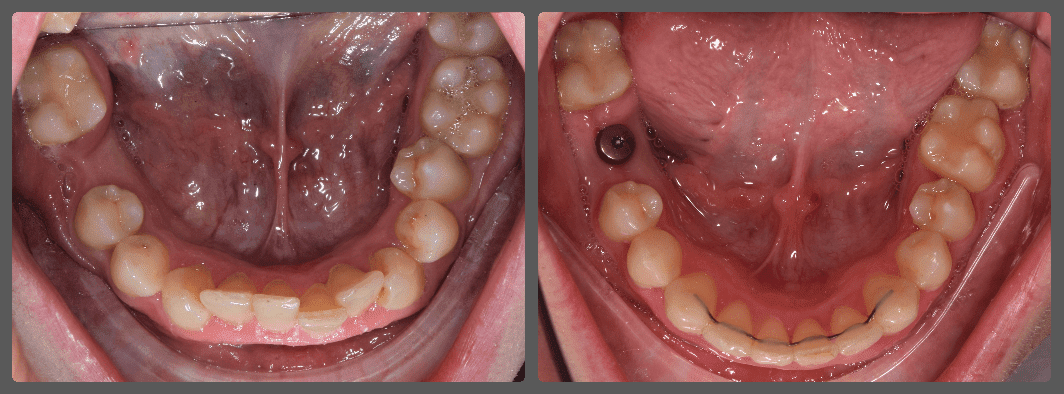

Bálint a 90 fokban elfordult jobb felső kismetszője miatt keresett meg engem. A vizsgálatokat követően kiderült, hogy a probléma ennél jóval komplexebb: súlyos keresztharapást, súlyos mélyharapást és felső rágósík billenést diagnosztizáltam nála. Alsó-felső H4 önligírozó fogszabályozó készülék, intermaxilláris gumihúzás és elülső harapásemelők segítségével korrigáltuk az eltéréseket. A bal oldali rágósík billenést fogszabályzási miniimplantátum alkalmazásával oldottuk meg. A bal felső-elülső fogakat felfelé mozgattuk, a miniimplantátumhoz húzva. Bálint esete igen komplex volt, ám kiváló együttműködésének köszönhetően 26 hónap alatt végeztünk a kezelésével (beleértve a 2-3 hónapos COVID-19 miatti leállást is). Az eredmény úgy gondolom magáért beszél!